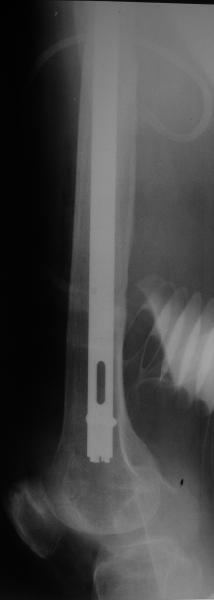

Спасибо за обсуждение. После нескольких дней тракции аппаратом сделали. Попытка закрытой репозиции не удалась из-за смещения по ширине, мешали фрагменты цемента. После их удаления репозиция получилась. Еще убрали немного цемента с ножки по латерльной стороне, чтобы обнажить 40-50 мм ее дистальной части, для плотной посадки гвоздя. Дальнейшее введение гвоздя было несложным. Протез показался нам стабильным в проксимальной части как латерально, так и медиально. Картинки в приложении.

THX for the discussion. After few days of traction by ex-fix the surgery was performed. An attempt of closed nailing was unsuccesful because of fragment translation, which was blocked by cement fragments. After removal of broken cement pieces reduction was reached "automagically". Also some cement from lateral part was removed by

chisel to expose distal 40-50 mm of the stem to allow tight fit of the nail. Further fixation by the nail was pretty easy and straightforward. Images attached. The stem looked stable in its proximal part both laterally and medially. Comments/critics are welcome.